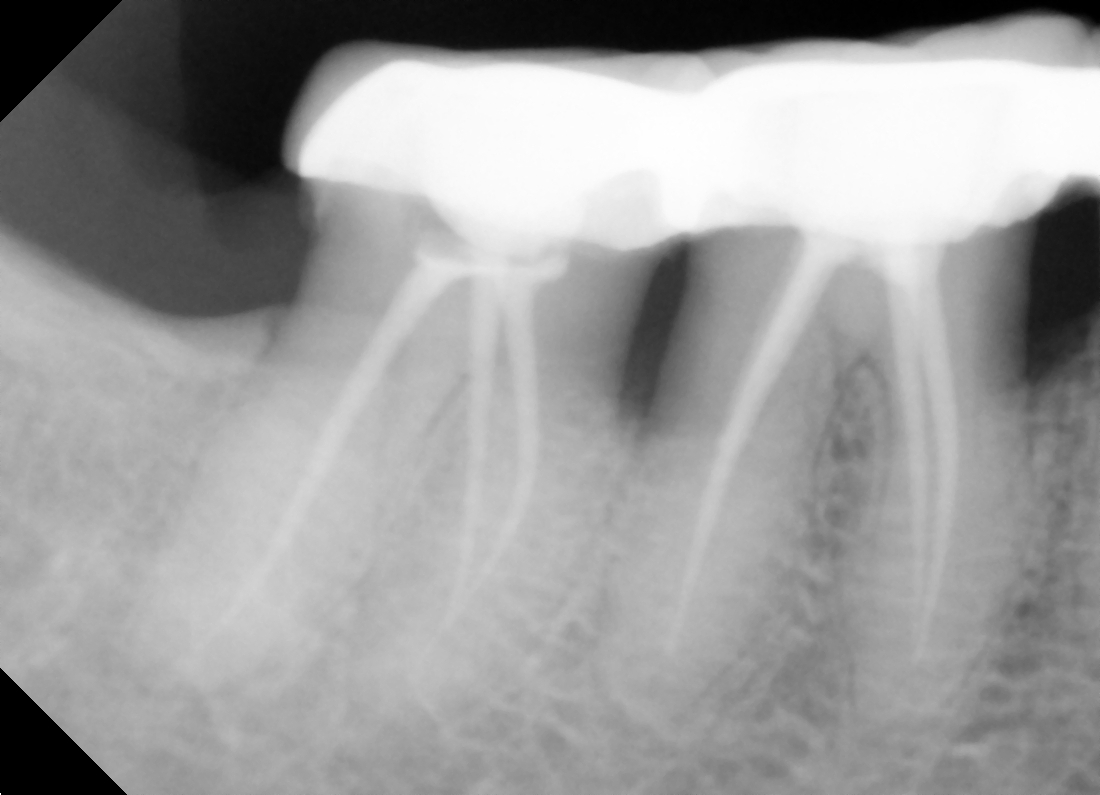

Is crown required?

Depending on the tooth, it is quite common to recommend placing a crown over the tooth within 3 months after root canal treatment, to provide maximum protection for the tooth in the long term.

The reason for this is because a tooth that has undergone nerve infection and pulp is removed thus tooth has become weak and brittle. A lot of biting forces fall on teeth when we eat and chew, so placing a crown on the tooth provides the tooth the necessary strength and durability.